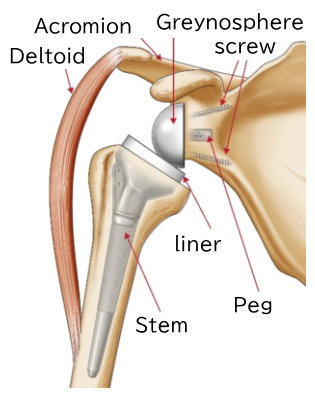

Reverse total shoulder arthroplasty involves implanting specialized components into the shoulder blade (scapula) and upper arm bone (humerus), as shown in the illustration below.

In this procedure, a plastic socket (liner) and stem are placed into the deformed humerus, while a metal ball (glenosphere) and baseplate are attached to the glenoid cavity of the scapula. The baseplate is secured using metal screws.

The diagram below shows the reverse shoulder prosthesis implanted into the humerus and scapula. The stem and liner are connected as a single unit.

The diagram below shows the baseplate implanted into the glenoid cavity of the scapula.

However, in reverse total shoulder arthroplasty, the ball component called the glenosphere is placed on the glenoid (socket) side, and the socket component is attached to the humeral side. In standard total shoulder arthroplasty, the ball is attached to the humerus, and the socket is implanted into the glenoid cavity. In the reverse procedure, the positions of the ball and socket are switched.